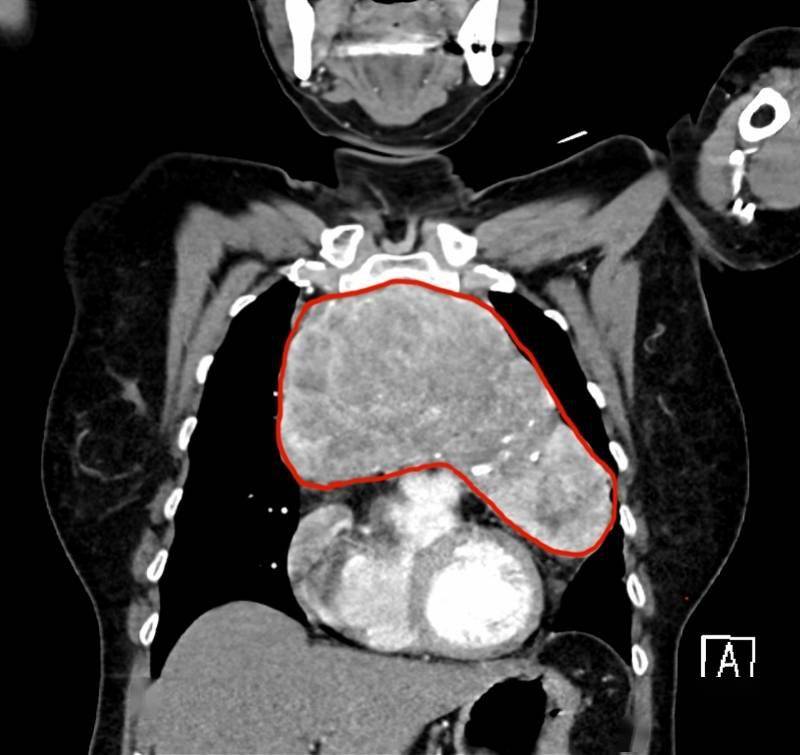

据林婆婆回忆 , 自己13年前曾做过一次子宫脱垂手术 , 术前检查已发现胸骨后甲状腺肿 , 但由于肿物不突出颈部 , 且没有特殊症状 , 一直没有太在意 , 也就没有治疗 。 但近几年来 , 林婆婆渐渐出现了面色潮红、不能平卧的状态 , 晚上只能半坐着睡觉 , 无法躺平 。 这背后的“罪魁祸首”正是不断增大的胸骨后甲状腺肿 。 近期复查CT检查显示 , 林婆婆的胸骨后甲状腺肿将心脏往下挤压 , 使得支气管变窄 , 就像一块顶心又顶肺的“大石头” 。

为了移开这块“心头大石” , 林婆婆辗转省内多家医院 , 最后来到了中山大学孙逸仙纪念医院耳鼻咽喉头颈专科 , 由咽喉头颈专科主任梁发雅副教授接诊 。 梁发雅副教授阅片后 , 发现胸骨后甲状腺肿已经长到了18厘米长、16厘米宽 , 且肿物的生长时间长 , 已经压迫气管和血液回流心脏的上腔静脉 , 形态为上窄下宽 , 难以单纯经颈部完成手术 。

CT显示甲状腺肿主体位于胸腔 , 与心脏及周围血管关系密切 , 上腔静脉受压迫